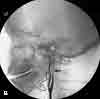

The initial CT scan of the brain showed a linear hyperdensity in the region of the left middle cerebral artery, which indicated thrombus formation (Figure 1). An area of cerebral edema was noted in the region with a small effacement from left to right. A cerebral angiogram performed 6 hours after the CT scan revealed a complete dissection of the left internal carotid artery (ICA) from the second cervical segment craniad (Figure 2). A follow-up CT brain scan 24 hours later demonstrated a large, left middle cerebral artery ischemic infarction with midline shifting and evidence of left uncal herniation (Figure 3).